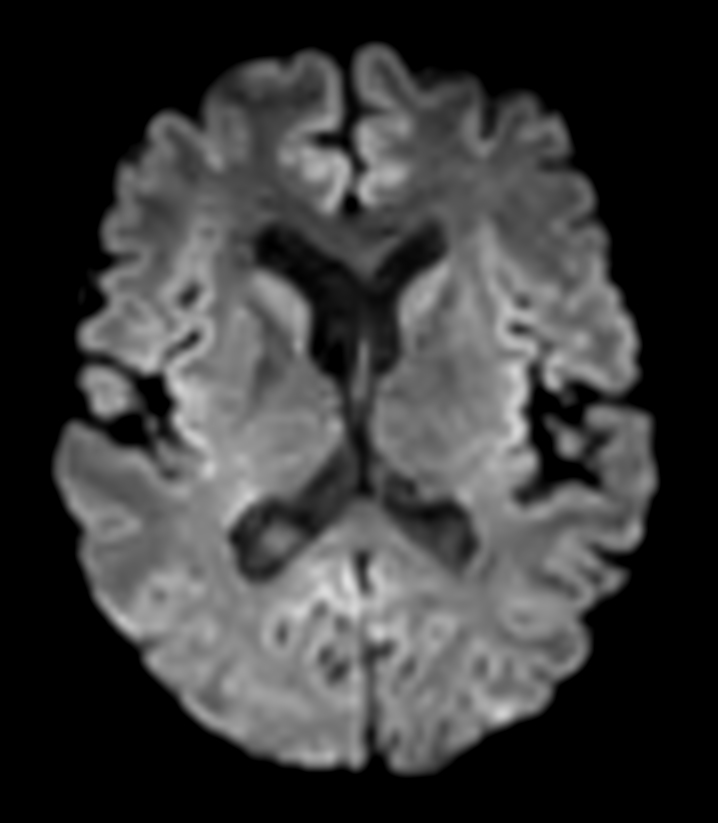

DWI b1000

-